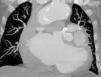

Transthoracic echocardiography performed at the patient's bedside showed moderate depression of left ventricular systolic function (40% ejection fraction) and severe mitral regurgitation. Since abdominal aortic aneurysms are frequently associated with clinically significant coexisting coronary artery disease, after hemodynamic stabilization coronary angiography was performed. This showed multiple aneurysms involving all the main coronary arteries without significant stenosis (Figure 1). To better assess the coronary arteries cardiac computed tomography was performed, which showed a large aneurysm involving the anterior descending and circumflex arteries. The right coronary artery also had an aneurysm, smaller than in the left coronary (Figures 2 and 3).